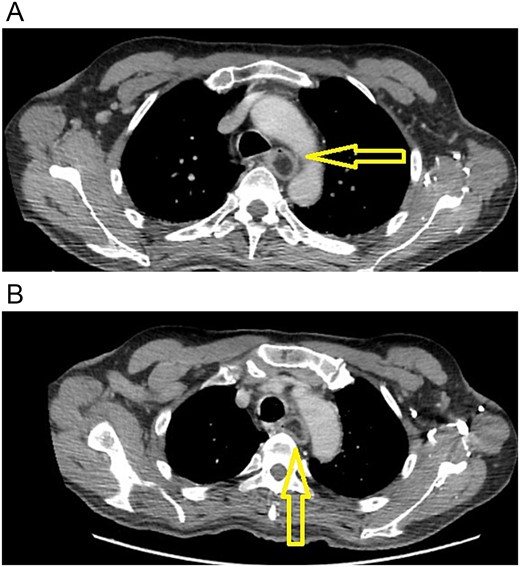

He partially recovered from the hemiplegia and neurologic sequelae, but he became completely care dependent. One thing that worsened during this time was his dysphagia; he did not have any neurogenic dysphagia; nevertheless, he was unable to drink anything, and it became so severe that he was unable to swallow saliva. Therefore, one year later, he presented to our office. A new endoscopy revealed that the giant polyp completely obstructed the lumen of the esophagus, and a new chest CT showed that the polyp grew but did not invade any surrounding structures (Fig. 2).

(A) Endoscopy, the polyp obstructs the esophagus's lumen. (B) CT scan: esophageal polyp size has increased in size over a year.